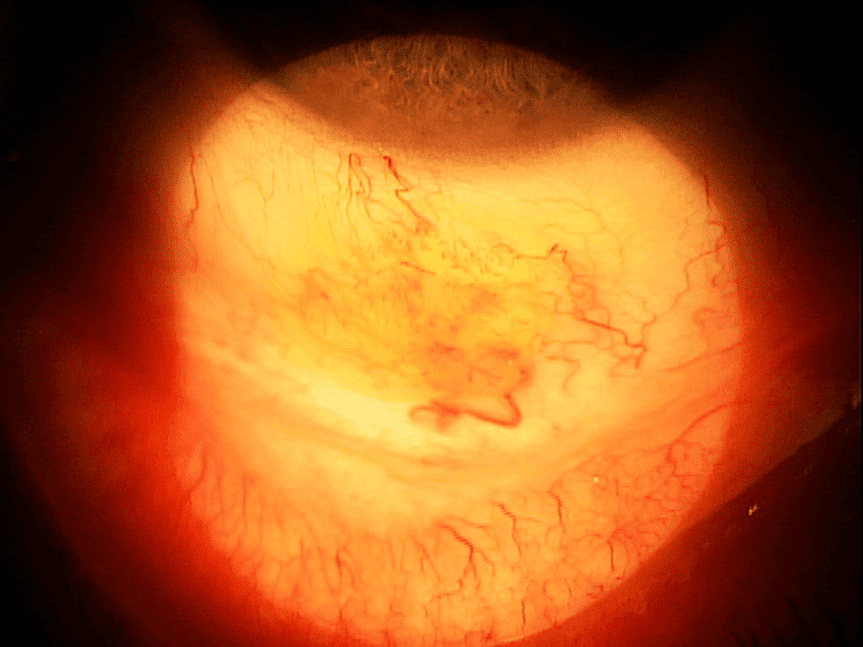

Previous record review showed the initial conjunctival lesion was removed via shave biopsy, and the pathology report confirmed a squamous papilloma. An anterior segment photo of the lesion prior to excision was included (Figure 1).